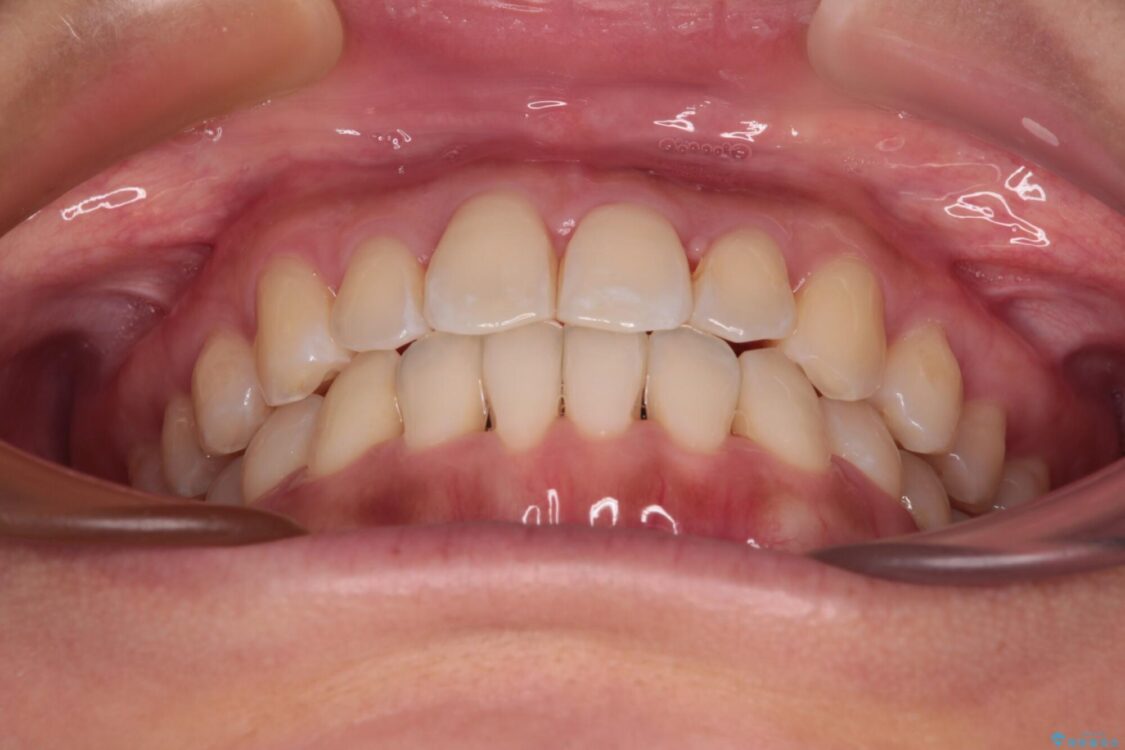

前歯のデコボコで前方に出ていることを気にして来院された患者様です。

上顎前歯が捻れて前方に飛び出しており、下顎前歯もそれに沿うようにデコボコとなっていました。

• 【モニター】前歯のデコボコをインビザラインで改善 治療前画像